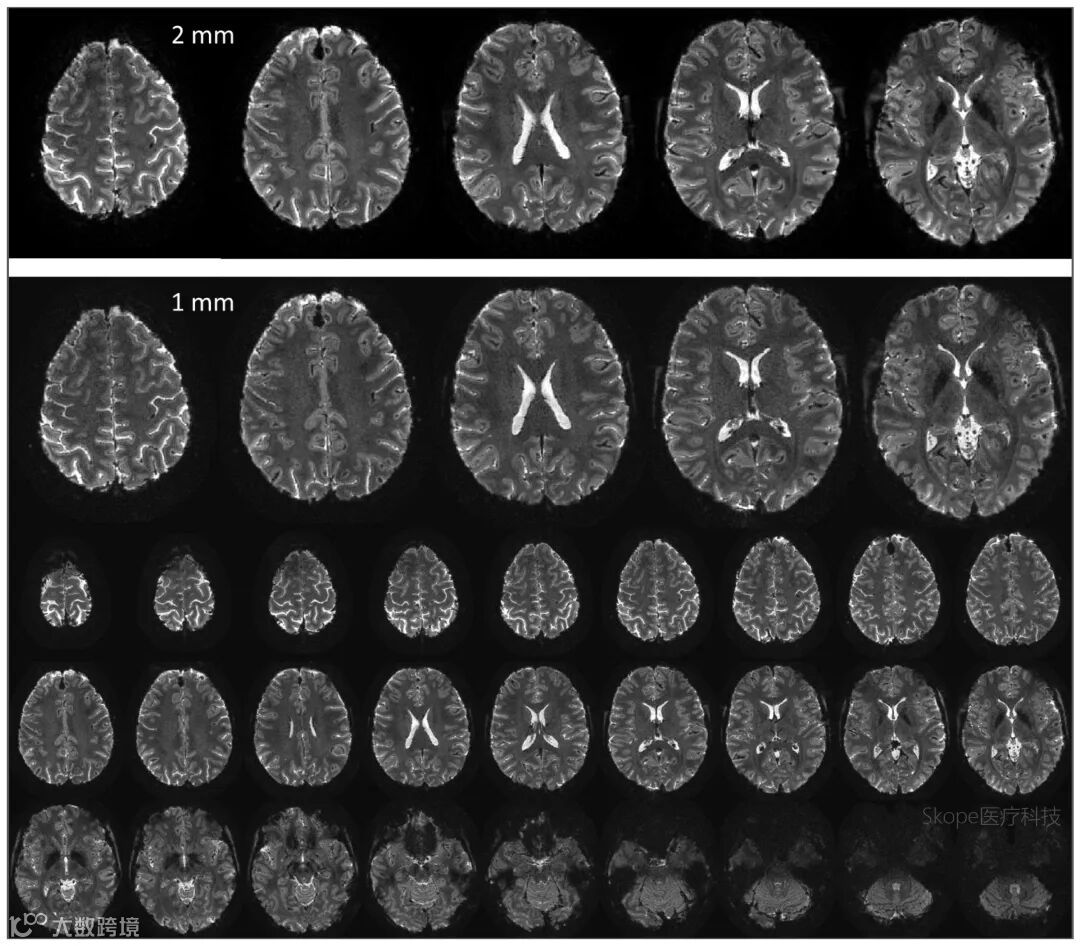

在2 mm厚度切片中,图像结构清晰,灰质/白质及脑-脑脊液边界可见度高,未出现传统螺旋采集中常见的模糊或形变问题。即使在切片厚度缩小至1 mm、SNR下降的条件下,图像仍保持良好细节表现。

高分辨率单激发螺旋图像(平面分辨率0.8 mm,读出时长53 ms)。

上排为5个2 mm层厚的切面,下排为1 mm薄层。图像中灰白质及脑脊液边界清晰,无明显模糊或几何畸变